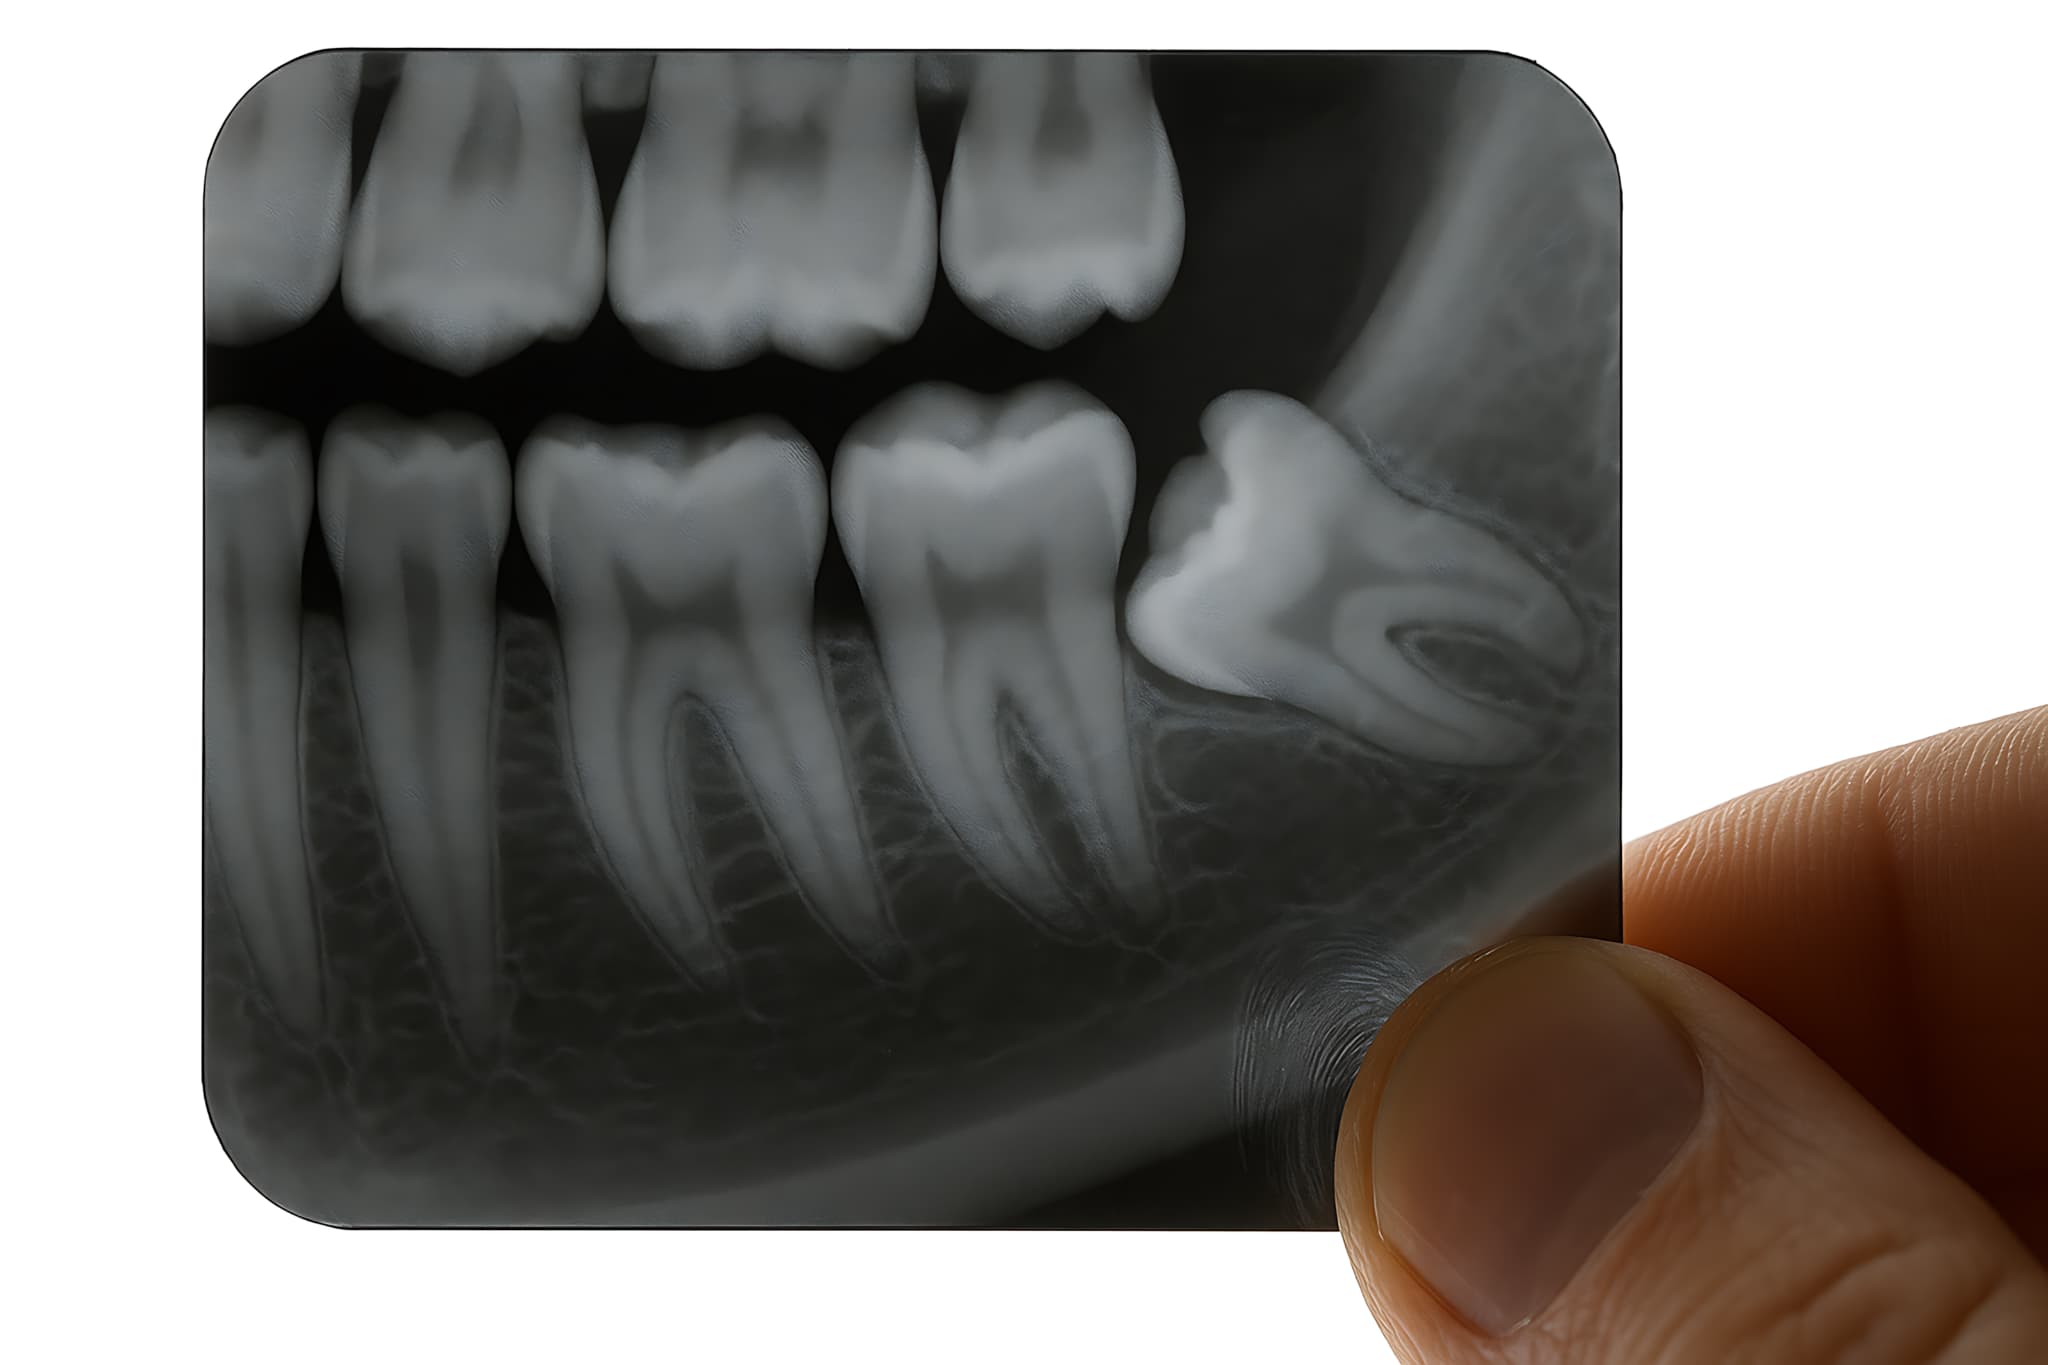

顎の骨や歯列のスペースが不足しがちなため、親知らず(第三大臼歯)は斜めに生えたり横向きになったりすることがあります。特に、下の親知らずは顎の骨に埋まっていることが多く、歯茎の一部からしか見えない半埋伏の状態もよく見られます。

口内の状態確認

まずはレントゲン検査を行い、親知らずの生え方や斜めに生えている角度、周囲の歯への影響などを詳しく確認します。また、虫歯や歯周病の有無、歯茎の炎症の程度なども把握します。これによって、抜歯の必要性と抜歯方法、抜歯のスケジュールを判断します。

検査

まずは、親知らずが斜めに生えている理由や今後の見通しを含めた、詳細な検査を行います。CT検査やレントゲン検査などで親知らずの位置や向き、隣接する歯との位置関係などを詳しく調べます。